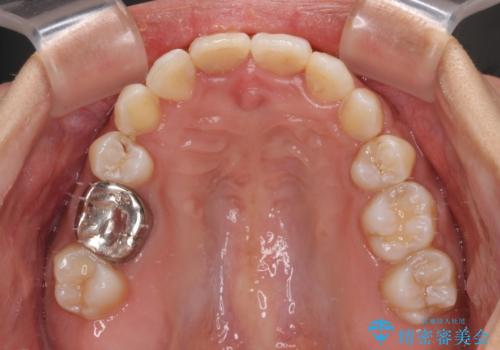

- 八重歯や前歯のデコボコを気にして来院された患者様です。

目立たない装置を希望されたので、上顎が裏側装置のハーフリンガルを選択し、上下左右の小臼歯(計4歯)を抜歯して矯正治療を行うこととしました。

補助装置を併用することで、八重歯を速やかに改善し、治療期間の短縮を図ることとしました。